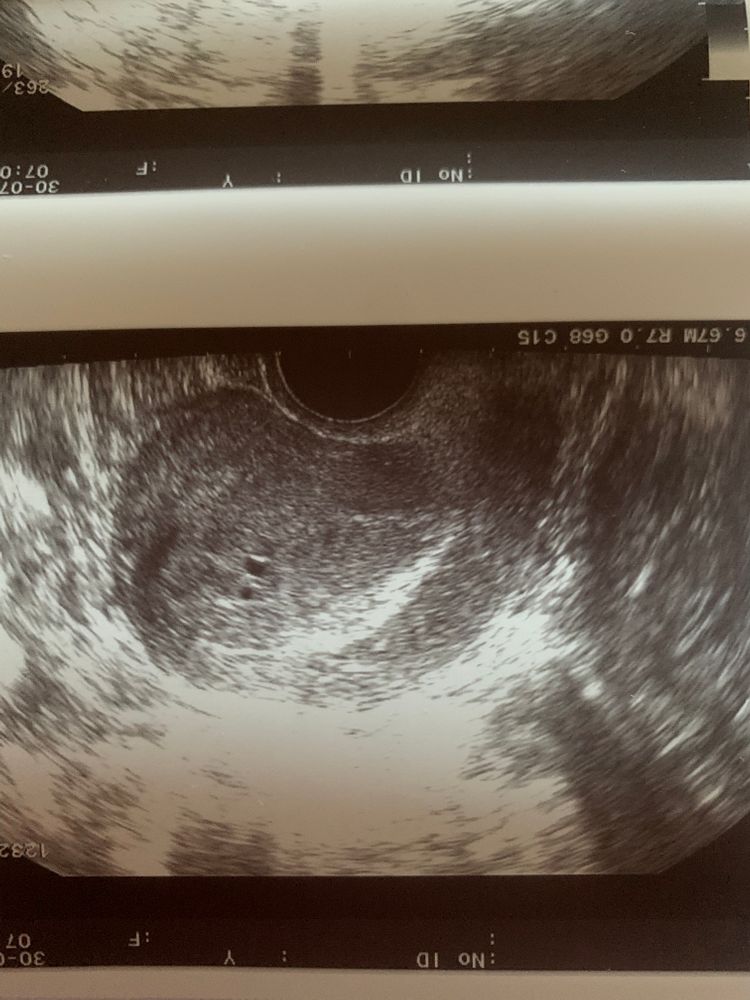

Kate Agaeva, я не знаю 🙈 гинеколог это назвала беременностью, а вот фотка с узи Ре сегодня (там обе видно), он говорит что то что на фото, свидетельствует о том что была имплантация, у меня уже мозг кипит🤯. Также говорит что это выйдет вместе с месячными. а те кисты о которых вы говорите, могут быть из-за процедуры эко в целом? У меня ничего подобного никогда не было Изображение

вероника, забила, ни одной похожей на мое узи картинки Изображение

Здравствуйте, сразу скажу вам я врач, врач УЗИ. То что на фото это не кисты в эндометрии, а полости жидкостные, встречаются часто перед месячными прям за пару дней, можно принять за беременность малого срока конечно, но ХГЧ уже должен быть более 600 ЕД, но эндометрий в 18 мм это не норма, а эти самые полости ещё раз это подтверждают (возможно воспалительные)! Какая бы поддержка не была более 16 это гиперплазия, и имплантации у вас не было. Ни о каких субмукозных узлах тут речи не идёт (судя по фото) не слушайте местных экспертов :) я бы проверяла эндометрий точно. И скажите на какую толщину переносили?

LeLu, Очень похоже на субмукозный узел

LeLu, Забейте: Субмукозный узел в сагитальной плоскости, очень похоже